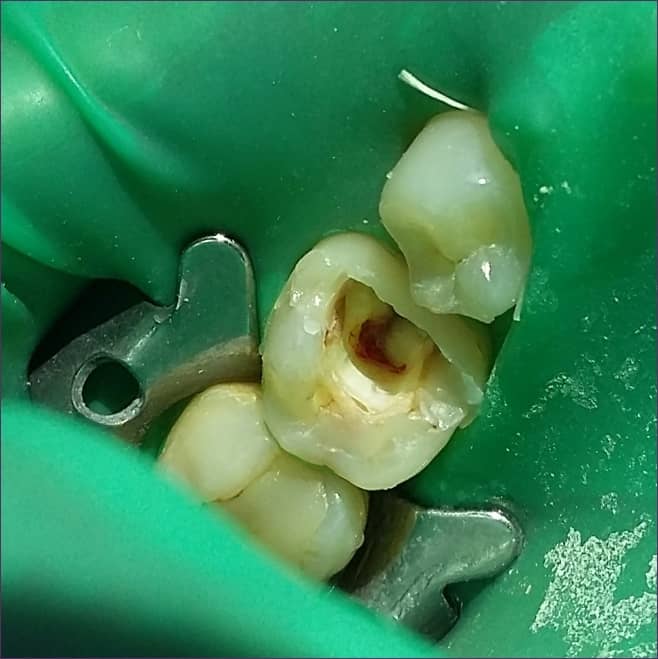

3, A fogait speciális gumilepedővel vonjuk körül

A kofferdam-izoláció azt a célt szolgálja, hogy a kezelés alatt a fogai ne érintkezzenek nedvességgel, nyállal (ezáltal baktériumokkal), vízzel, és minél jobb munkakörülményeket biztosítson a kezelőorvosnak.

Fontos továbbá annak biztosítása, hogy az általunk, a fog belsejének megtisztítására használt anyagok ne jussanak ki a szájüregbe.